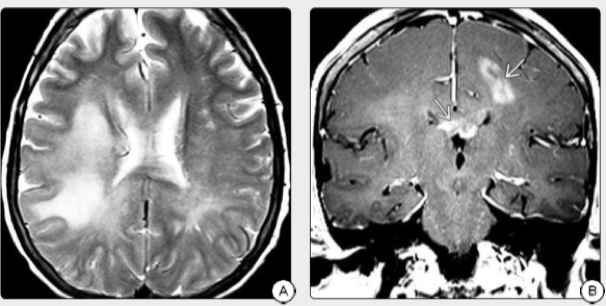

图2:A:T2WI在该老年患者中显示弥漫性融合性和斑块状高强度信号,并伴有混乱,左侧无力增加。B:同一患者的冠状T1显示左半球高信号肿块和胼胝体增强,活检发现弥漫性浸润性GBM。